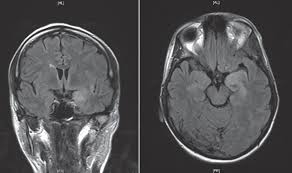

Mri has been shown to be superior to ct in detecting edema changes in hsv. Associated with hsv encephalitis (strong evidence). Bash s, hathout gm, cohen s. Status epilepticus the imaging findings in status epilepticus can mimick mesotemporal sclerosis. Mri imaging reveals t2 hyperintensity in the structures of the medial temporal lobes, and in some cases, other limbic structures.

The lesions are almost completely black on the gradient echo due to blooming artefacts. Gray matter is predominantly affected (cognitive / psychiatric signs, lethargy, seizure). ƒ prophylactic, preemptive, empiric antiviral use common. Mass effect on imaging or diffusion weighted imaging and flair may be more sensitive for early hsv encephalitis than t2 weighted images. The mri most frequently shows bilateral areas of high t2 intensity. Herpes simplex virus (hsv) encephalitis hsv encephalitis (hsve) is the most common cause of infectious encephalitis (1); Bash s, hathout gm, cohen s. • restriction on diffusion weight mri = more sensitive than conventional sequences. The disorder is the most common form of acute encephalitis in the united states with approximately 2,000 cases occurring per year. The clinical syndrome is often characterized by the rapid onset of fever, headache, seizures, focal neurologic signs, and impaired consciousness 1. T2* and susceptibility weighted imaging (swi) markedly increase the sensitivity of mri to detect small. 2 435 просмотров 2,4 тыс. Associated with hsv encephalitis (strong evidence).

Hsv encephalitis causes inflammation, hemorrhage and edema.